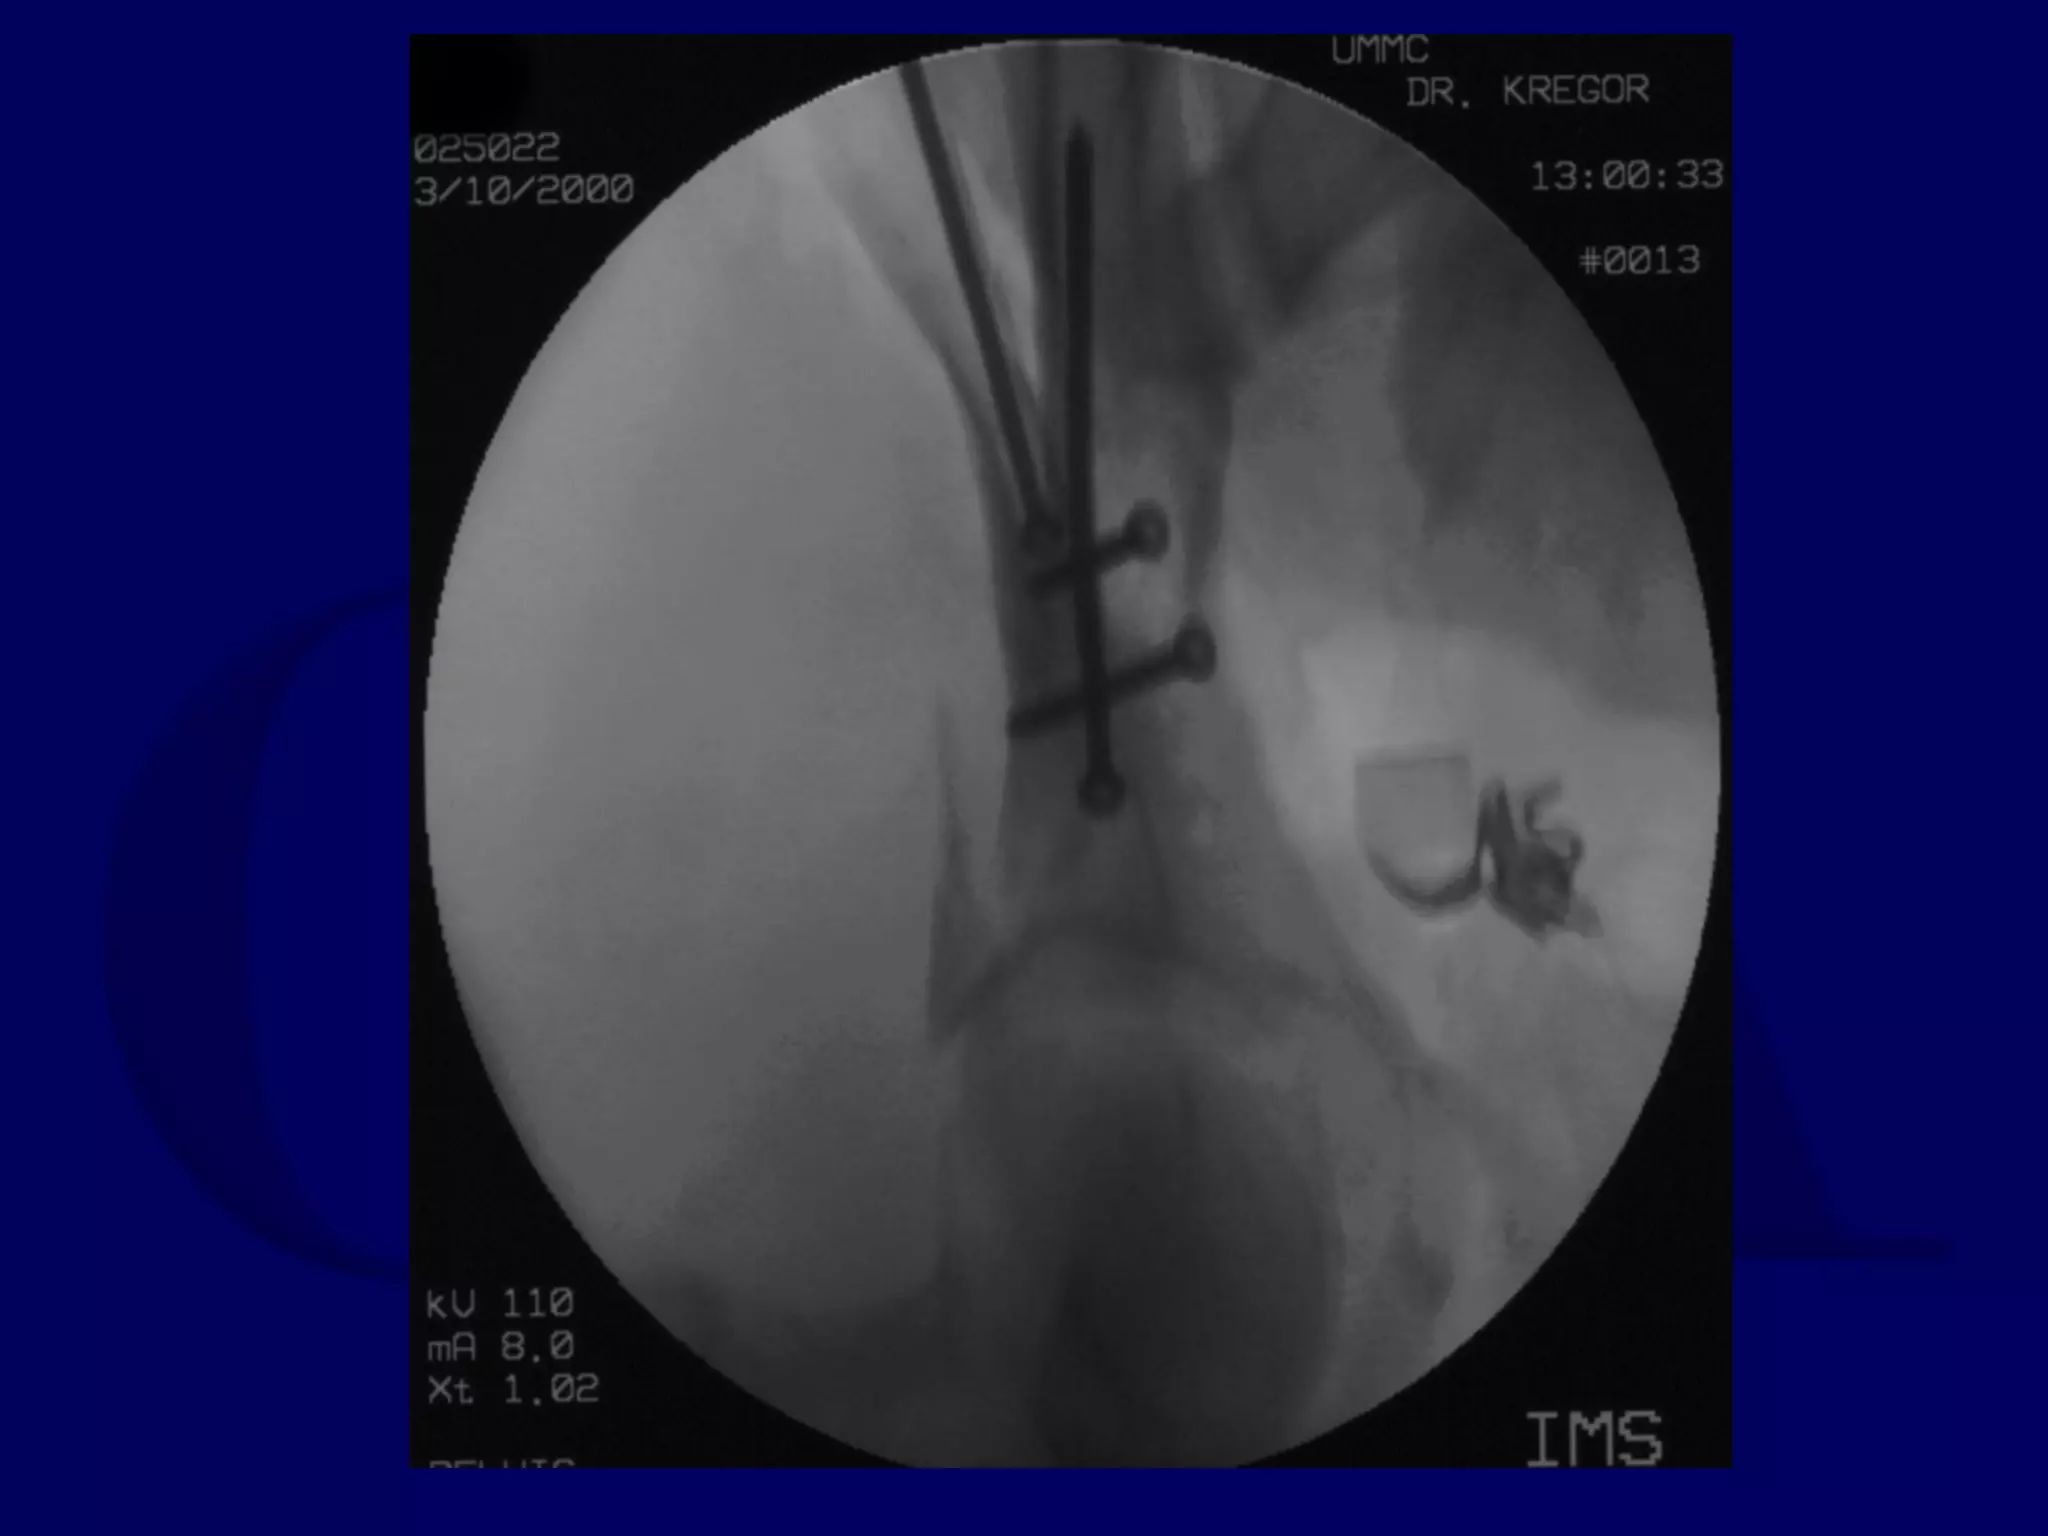

R.C. 00.03.10

Special Case

“T-Type” Acetabular Fracture

Proximal Femur Fracture

14 y.o. Male

Sequential K-L / Ilioinguinal

Initial Kocher-Langenbeck

Approach

P.J. 00.12.18

Subsequent Ilioinguinal

P.J. 00.12.22